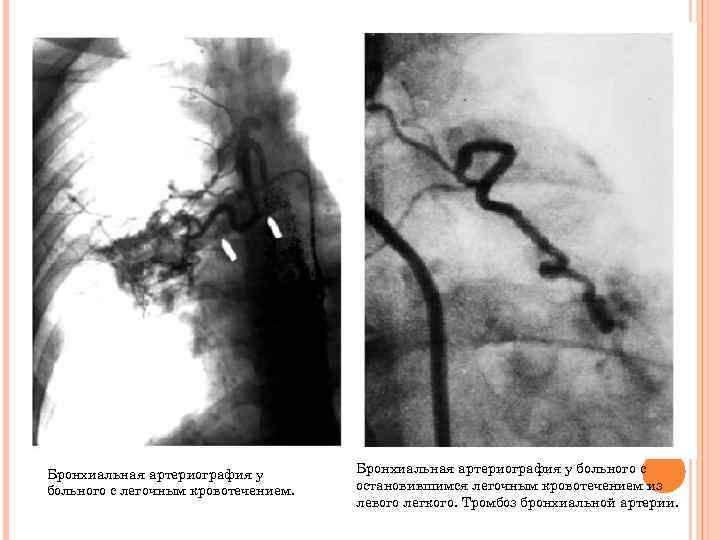

Бронхиальная артериография у больного с легочным кровотечением. Бронхиальная артериография у больного с остановившимся легочным кровотечением из левого легкого. Тромбоз бронхиальной артерии.

Бронхиальная артериография у больного с кровотечением из правого легкого. Гиперваскуляризация с выходом контрастированной крови за пределы сосудов. Бронхиальная артериография у того же больного после окклюзии периферического отдела бронхиальной артерии. Кровотечение остановлено.